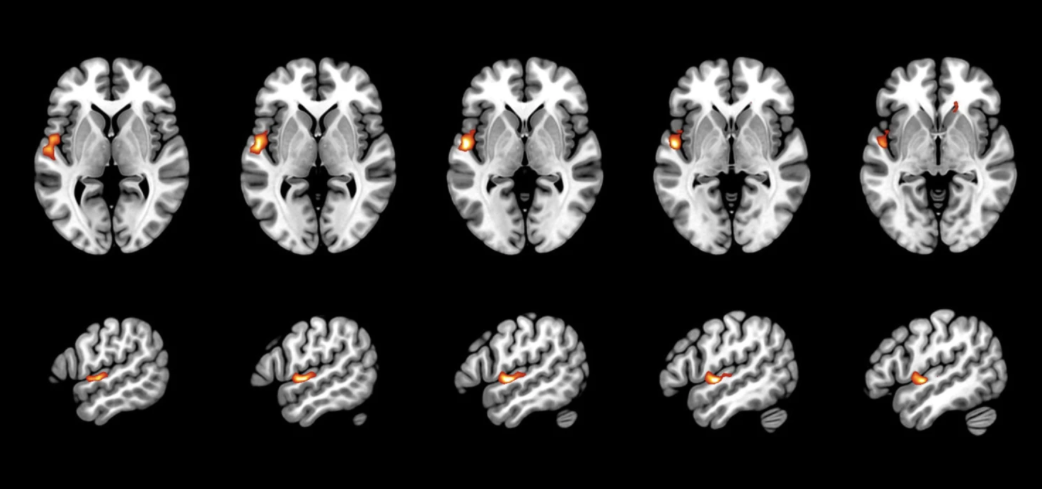

New paper: In utero effects of prenatal alcohol exposure

Feb 17th 2023: new paper on detecting initial in utero effects of prenatal alcohol exposure with help of fetal MRI based brain atlas analysis published by Marlene Stümpflen and colleagues in Cerebral Cortex.

More